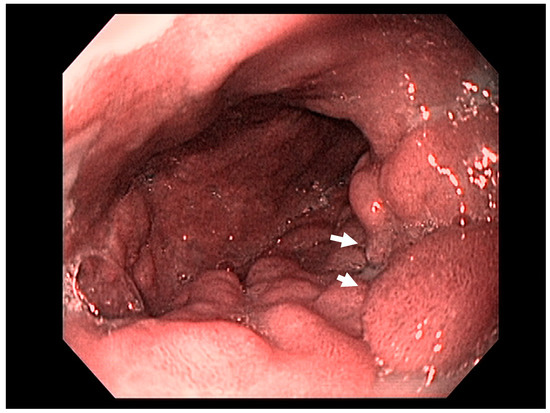

4.3. Endoscopic Ultrasound in Staging of Gastric Cancer

- Adam, B.; Pech, O.; Steckstor, M.; Tannapfel, A.; Riphaus, A. Gastric Mucosa-Associated Lymphoid Tissue Lymphoma. Video J. Encycl. GI Endosc. 2013, 1, 174–175. [Google Scholar] [CrossRef][Green Version]